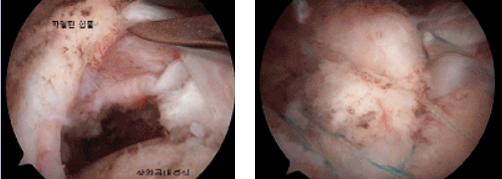

회전근힘줄의 파열 (좌 : 파열 / 우 : 봉합후) 회전근개파열 이미지